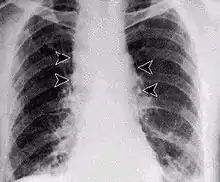

الجمرة الخبيثة الرئوية

عدوى الجهاز التنفسي لدى البشر في البداية تبدا مع البرد أو باعراض تشبه اعراض الانفلونزا لعدة أيام، تليها انهيار شديد (وغالبا ما يكون مميتا) في الجهاز التنفسي. تاريخيا كان معدل الوفيات بنسبة 92 ٪، ولكن عندما عولج مبكرا (انظر في هجمات عام 2001 الجمرة الخبيثة) : بلغت الوفيات بلغ 45 ٪.[15] وفي حالة تطور المرض إلى مرحلة المداهمة تكون نسبة الوفيات بنسبة 97 ٪ بغض النظر عن العلاج.

وتفيد التقارير ان العدوى القاتلة تنجم عن استنشاق ما يقرب من 10,000- 20,000 من الجراثيم، على الرغم من هذه الجرعة تختلف بين الأنواع المضيفة.[16] هناك تباين واسع مثل كل الأمراض لقابلية التأثير مع أدلة على أن بعض الناس قد يموتون من التعرض لأقل من ذلك بكثير، هناك القليل من الأدلة الموثقة على التحقق من العدد الدقيق أو متوسط من جراثيم اللازمة للعدوى. يعرف أيضا استنشاق الجمرة الخبيثة بمرض فارزي الصوف أو جامعي الثياب حيث أن هذه المهن هي أكثر عرضة للإصابة بالمرض بسبب تعرضهم للمنتجات الحيوانية الموبوءة. ومن الممارسات الأخرى المرتبطة بالتعرض تشمل تقطيع قرون الحيوانات لصنع الأزرار، ومعالجة الشعر الخشن الذي يستخدم لتصنيع الفرش، والتعامل مع جلود الحيوانات. غير معروف إذا كانت جلود الحيوانات هذه جاءت من الحيوانات التي نفقت بسبب المرض أو من الحيوانات التي كانت ترقض على أرض عليها البكتيريا. ويستخدم هذا النمط من العدوى في الأسلحة البيولوجية.